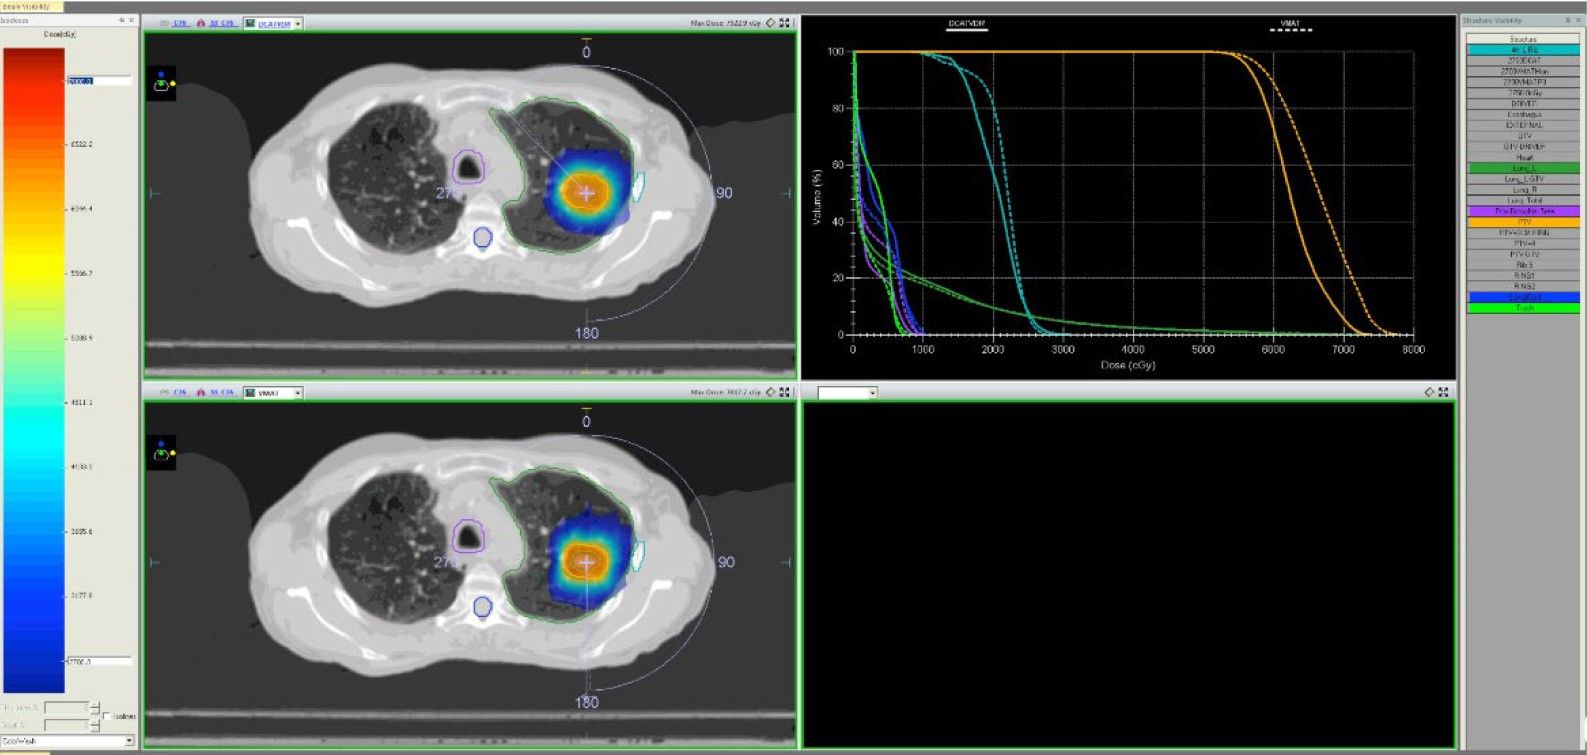

图2 &3:肺部SBRT病例(左)和肝脏SBRT病例(右)的优化DCAT(上)和VMAT(下)等剂量分布和剂量体积直方图(VMAT:实线,DCAT:虚线)的比较。

图2

VMAT和优化后的DCAT方案均达到了规划目标。虽然VMAT计划的目标覆盖率略好(VMAT平均PTVr = 1.3;DCAT平均PTVr = 1.4),这没有显示出统计学意义。同样,VMAT和DCAT的平均R50值非常接近(分别为4.5和4.6)。

总体而言,当桨叶重叠或接近PTV体积时,优化后的DCAT计划的质量低于VMAT计划,但当目标远离桨叶时,优化后的DCAT计划的质量与VMAT计划相当或更好。

与VMAT计划相比,优化DCAT计划中MU的平均数量减少了2.5倍(表2)。